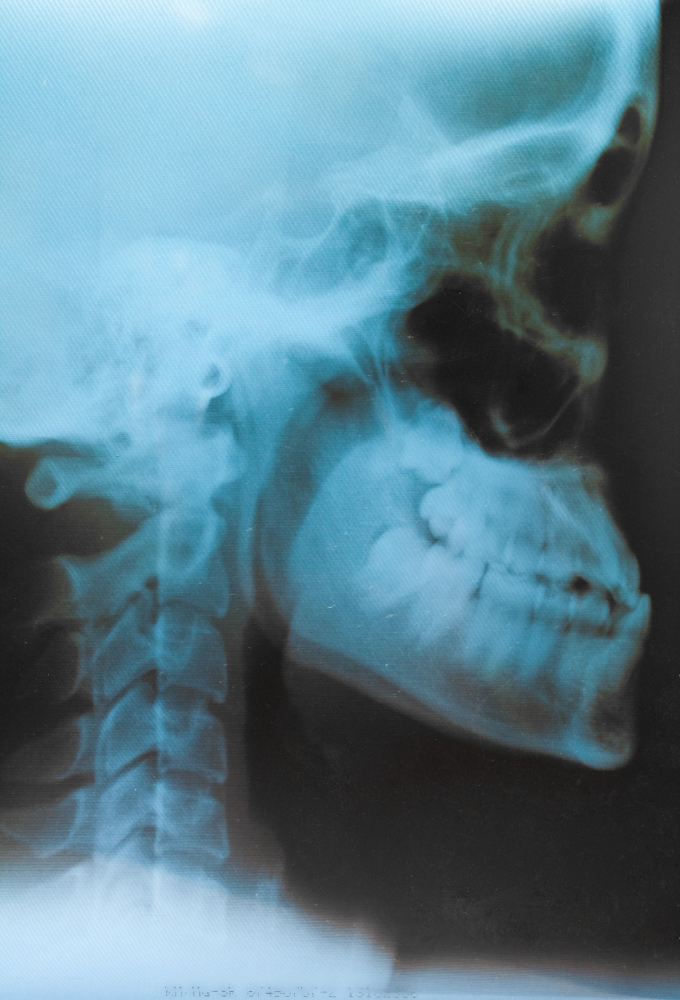

Skull AP & Lateral (2 Films) is a specialized X-ray test used to capture detailed images of the skull from two different angles – anteroposterior (AP) and lateral (side view). These views help radiologists examine the bones, structures, and sinuses of the skull for any abnormalities, fractures, infections, or developmental issues.

In the AP view, the X-ray beam passes from the front of the head to the back. In the lateral view, the beam travels from one side of the head to the other. The test usually takes 10–15 minutes, and the patient feels no pain during the process.

After taking both views, the images are analyzed by a radiologist to prepare a detailed report. This report is then reviewed by the treating doctor for diagnosis or further treatment planning.